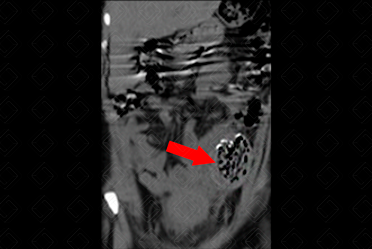

Texto alternativo para a imagem Créditos: Dra. Elazir Mota - Rio de Janeiro/RJ

Descrição das figuras : Tomografia computadorizada do abdome, sem administração do contraste venoso, evidenciando, na fossa ilíaca esquerda, presença de massa ovalada, com densidade de partes moles e contendo imagem linear, espontaneamente densa, podendo representar marcador de compressa retida (seta vermelha).

Exames de imagem: É de suma importância o radiologista ter conhecimento desse aspecto de imagem, para auxiliar no seu diagnóstico (figuras acima).

• Tomografia computadorizada (TC) do abdome ou tórax : Aspecto de uma massa heterogênea alongada contendo bolhas de gás e densidades metálicas intra-cavitária. A TC é o método de imagem mais eficaz para a detecção de um textiloma retido.